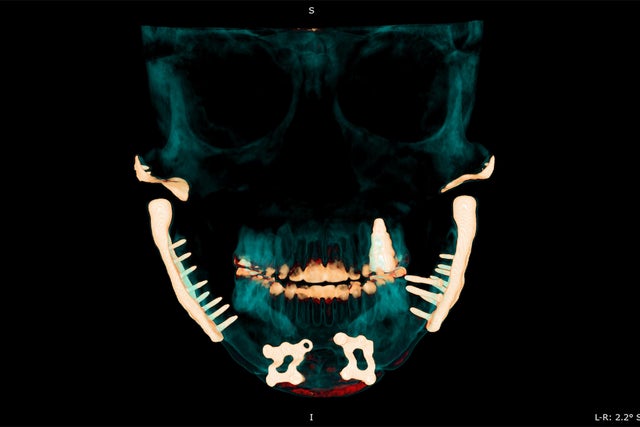

Plagued by TMJ symptoms, and after failed treatments, some patients turn to a last resort: replacing their jaw joint with synthetic implants. Surgeons might replace the cartilage disk at the core of the joint or use "total joint replacement surgery" to fasten a metal hinge to the bones of the skull.

But the implants have a harrowing history: Several disk implants were recalled or discontinued in the '90s due to dangerous failures. The FDA now classifies TMJ implants among its most closely monitored medical devices because the products on the market today can cause "adverse health consequences" if the devices fail, according to the agency's website.

Two companies, Zimmer Biomet and Stryker, make the only total jaw replacement implants currently sold in the U.S.

Zimmer Biomet, which has made its implant for more than two decades, described it in email statements as "a safe and efficacious solution" for patients who need their jaw joint replaced, either due to TMJ disorders, failed surgeries, injuries, or other ailments. An FDA-mandated study completed in 2017 found about 14% of patients who get the Zimmer Biomet implant require additional surgery or removal within 10 years, said agency spokesperson Carly Pflaum.

Kalinowski, the TMJ patient in Maine, has had portions of her jaw joint replaced six times, including receiving four implants. Her medical records show that the cartilage disk on her right side was replaced in 1986 with an implant that was later recalled and again in 1987 with another that was later discontinued. Her left and right disks were replaced in 1992 with a muscle flap and rib graft, respectively, and her entire right joint was replaced with yet another implant that was later discontinued in 1998. Both joints were replaced again in 2015, her records show.